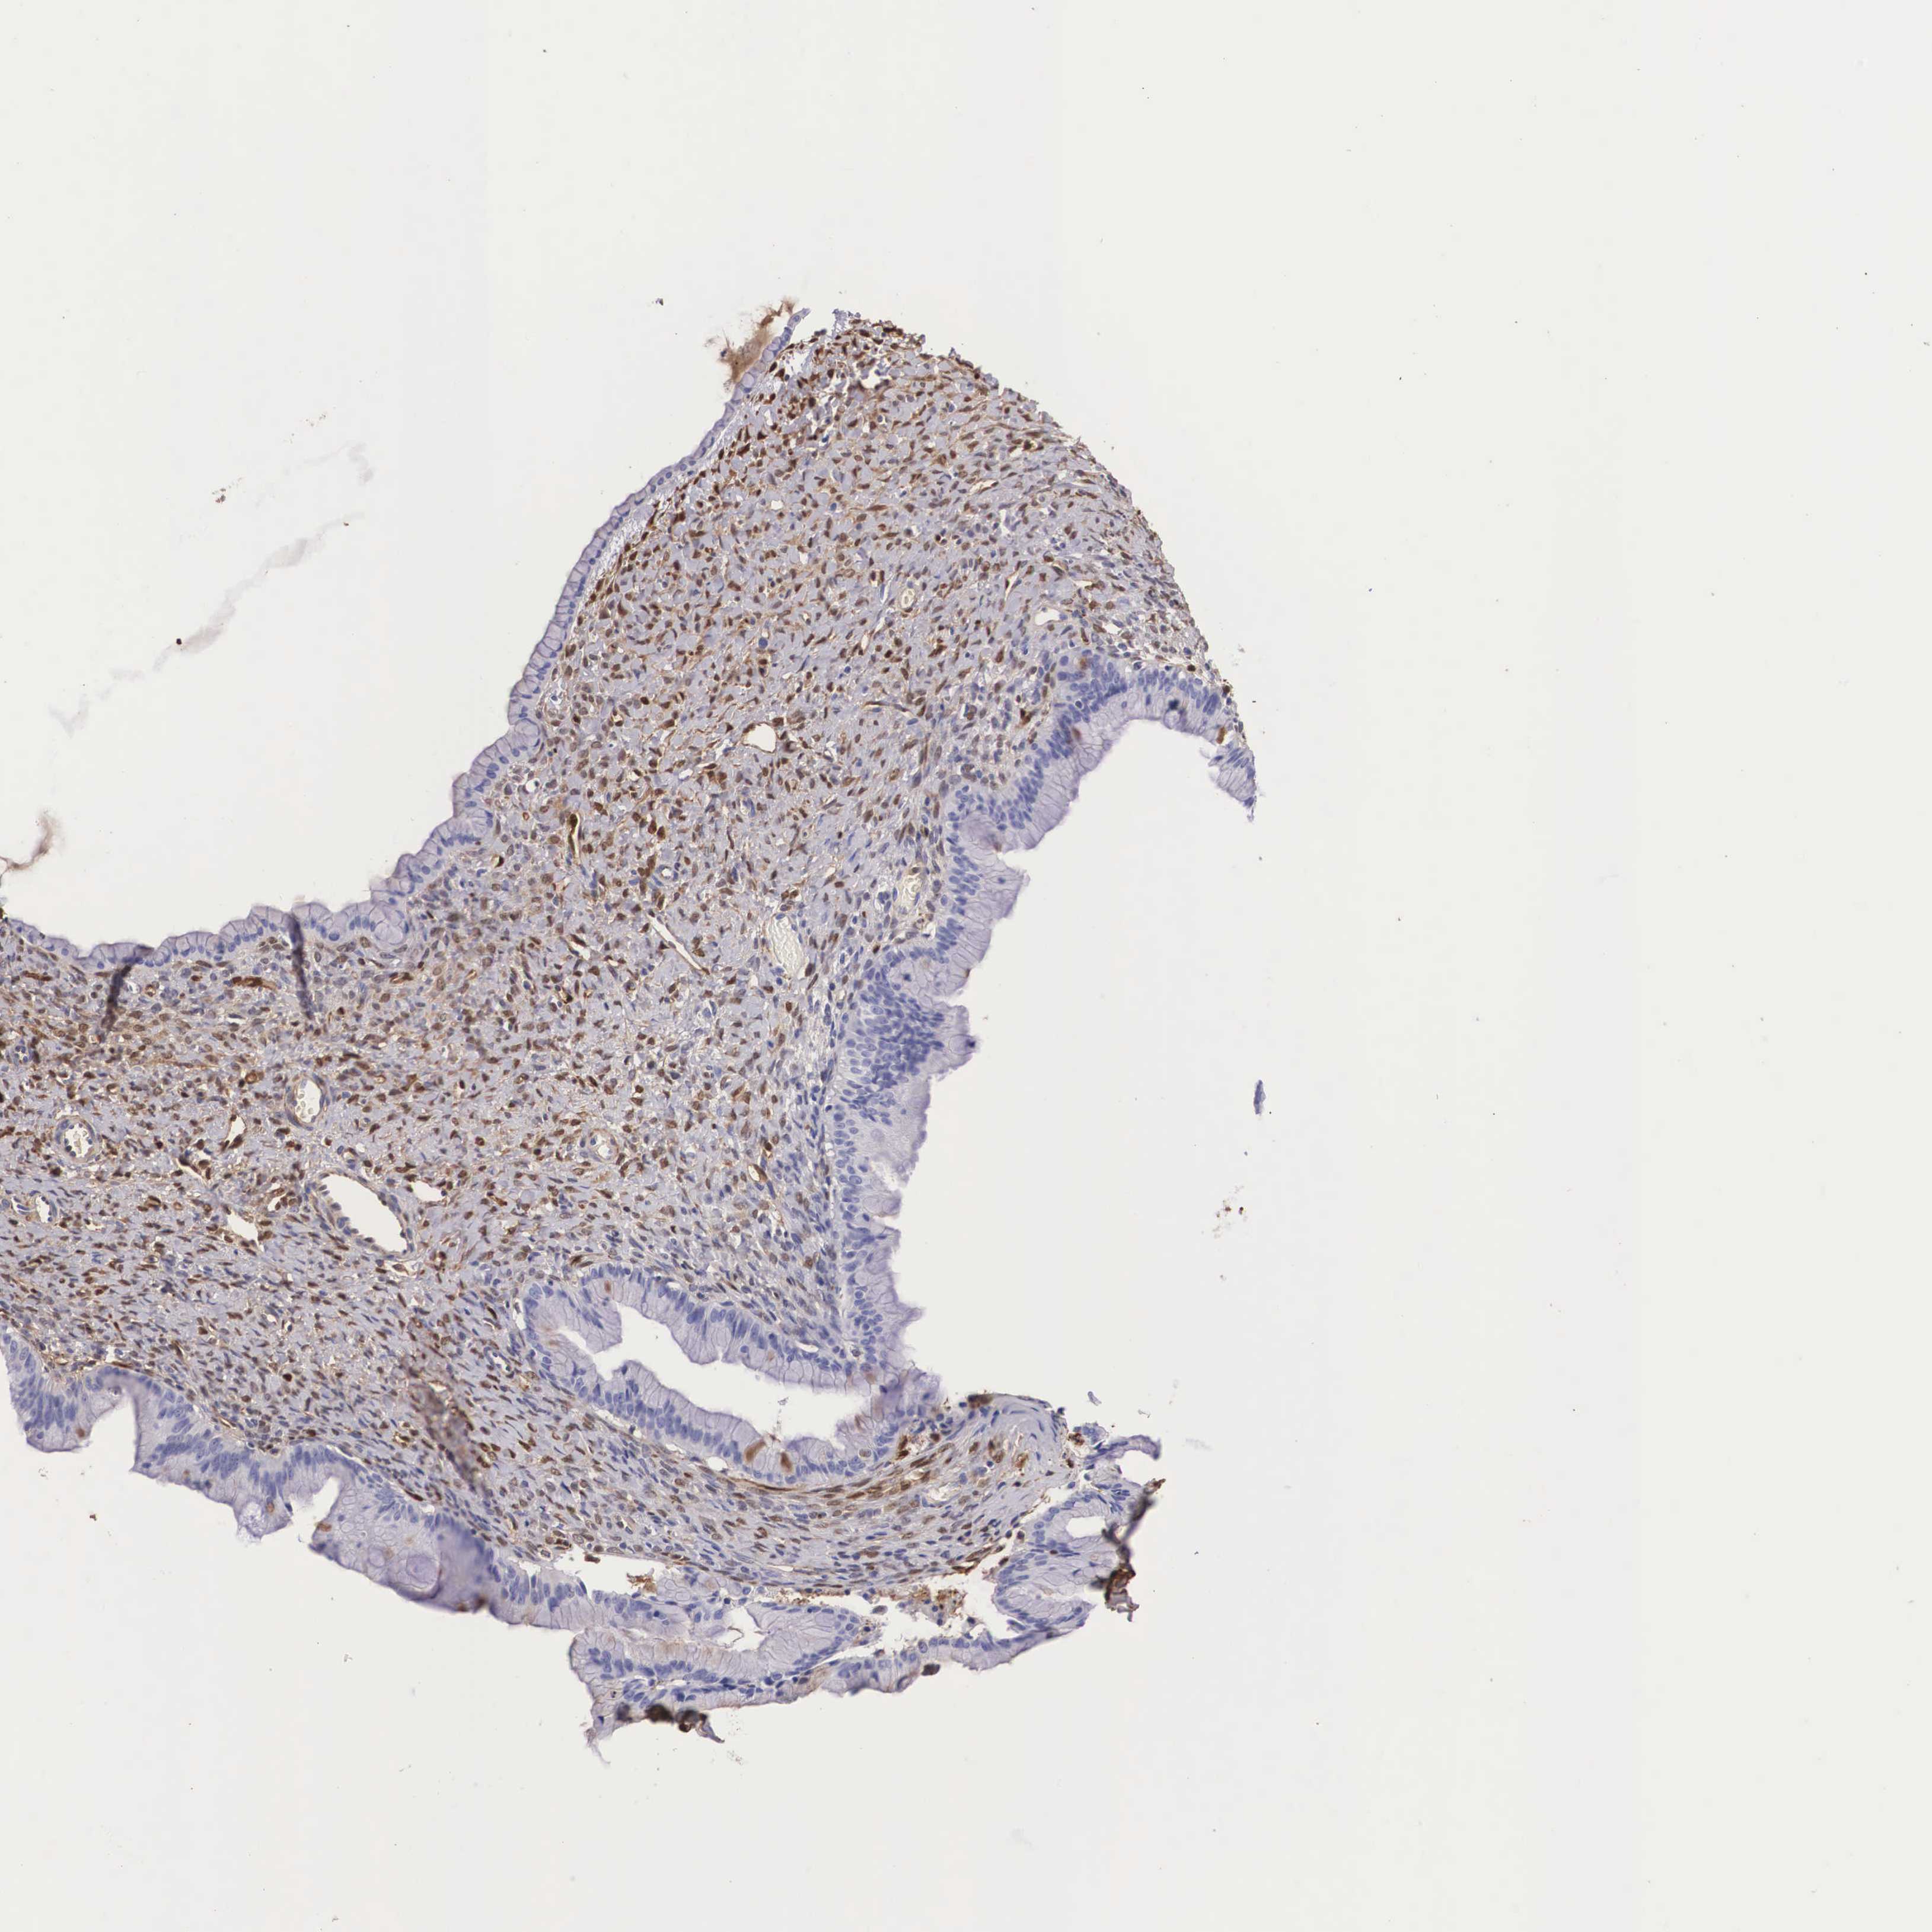

OVARIAN CANCER - Protein expressioni

A mouse-over function shows sample information and annotation data. Click on an image to view it in a full screen mode. Samples can be filtered based on level of antibody staining by selecting one or several of the following categories: high, medium, low and not detected. The assay and annotation is described here.

Note that samples used for immunohistochemistry by the Human Protein Atlas do not correspond to samples in the TCGA dataset.

Antibody stainingi

Antibody staining in the annotated cell types in the current human tissue is reported as not detected, low, medium, or high, based on conventional immunohistochemistry profiling in selected tissues. This score is based on the combination of the staining intensity and fraction of stained cells.

Each image is clickable and will lead to virtual microscopy that enables deeper exploration of all samples and also displays staining intensity scores, fraction scores and subcellular localization as well as patient and tissue information for each sample.

Antibody HPA000646

Antibody CAB002157

Staining

High

Medium

Low

Not detected

Intensity

Strong

Moderate

Weak

Negative

Quantity

>75%

75%-25%

<25%

None

Location

Nuclear

Cytoplasmic/membranous

Cytoplasmic/membranous,nuclear

Carcinoma, endometroid

Cystadenocarcinoma, serous, NOS

Cystadenocarcinoma, mucinous, NOS